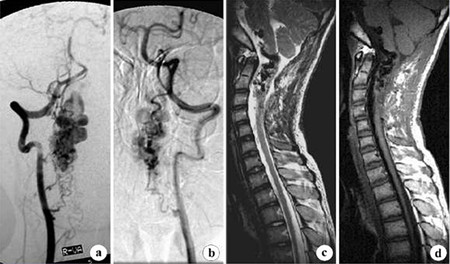

Ⅱ型為血管球狀畸形,在髓內(nèi)有一動(dòng)靜脈血管團(tuán),這些病變常常見于頸脊髓內(nèi),但也可發(fā)生于胸腰段的任何部位,其特點(diǎn)在血管造影中顯示為高血流量和稀疏的靜脈回流血管,常有靜脈瘤和靜脈曲張。